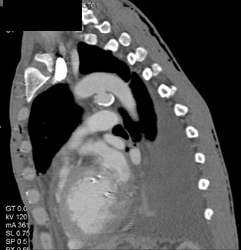

Diagnosis

Ductus Aneurysm